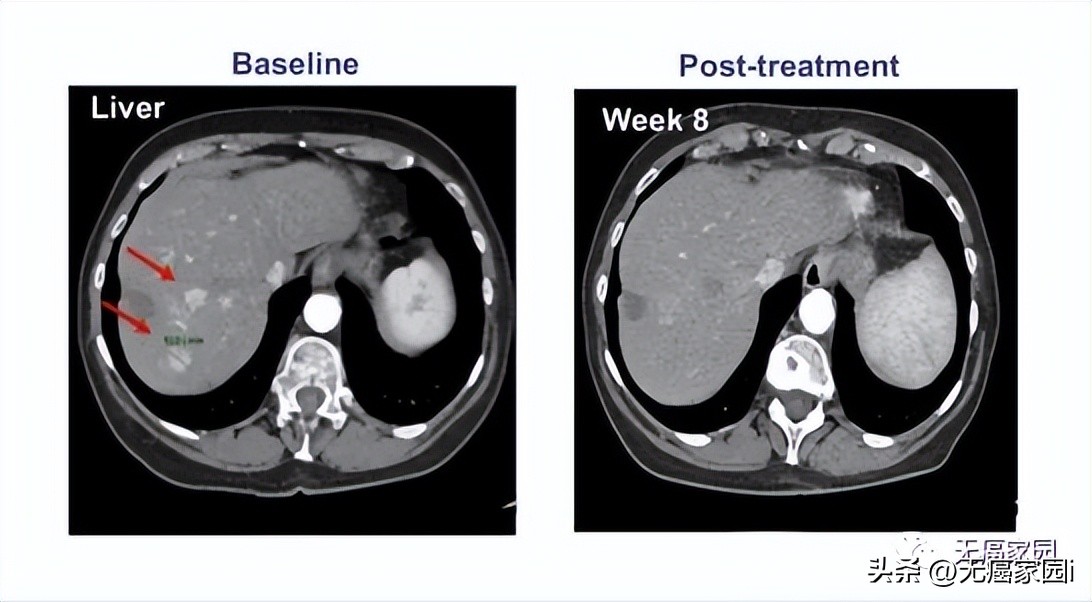

参与的9例患者均接受过手术及常规放化疗,但出现失败或不耐受的现象。在接受最高剂量治疗的4例患者中, 有1例患者获得完全缓解,CT扫描显示,患者体内所有病变都消失了,而且完全缓解后已持续半年以上无任何复发的状态!

在纳入的患者中, 有一名患者的癌细胞进程出现了完全缓解(CR)的表现,其余参与者的甲胎蛋白(AFP)也都出现了不同程度的下降, 这意味着试验取得了进展,也说明该疗法针对晚期肝癌的治疗是有效果的。